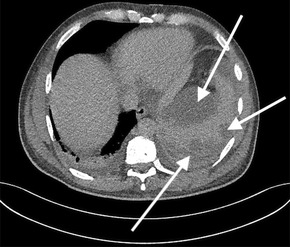

He completed seven days of broad‐spectrum antibiotics, and doxycycline was continued pending serology. A serial CT scan of the chest, abdomen and pelvis was performed to further investigate the cause of sepsis and demonstrated an incidental grade four splenic injury with peri‐splenic and subcapsular collections (Box 2). With a stable haemoglobin level, he was managed conservatively.

Box 2 – Grade four splenic injury with peri‐splenic and subcapsular collections

*The arrows indicate the splenic injury.